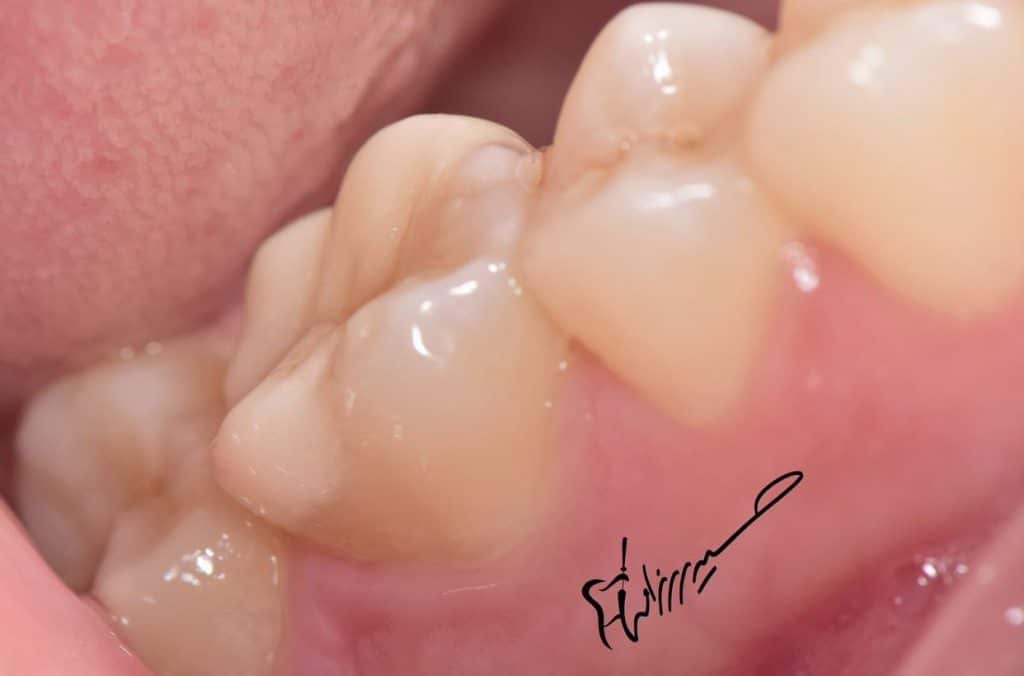

The palatal margin below the bone level ,

So surgical crown lengthening is the first step before margin elevation .

DME to get four walled tooth for better RCT and isolation.